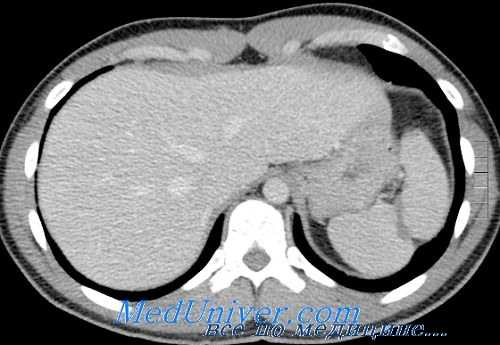

КТ – диагностика повреждений паренхиматозных органов, аорты, очагов кровоизлияний в брюшной полости и забрюшинном пространстве. Использование рентгеноконтрастных веществ (в/в или внутрь) расширяет возможности КТ и позволяет одновременно визуализировать паренхиматозные и полые органы брюшной полости. Повреждения почек и забрюшинные гематомы выявляют с помощью КТ живота, которую нужно провести каждому больному с гематурией и стабильной гемодинамикой (Уровень рекомендации - C)[3]. Необходимость проведения ИВЛ пациенту не является противопоказанием к КТ. Противопоказание - нестабильная гемодинамика пациента. Когда имеется подозрение на повреждение печени/селезенки КТ позволяет исключить повреждения требующие экстренного оперативного вмешательства (Уровень рекомендации - В) [3]. КТ рекомендуется у гемодинамически стабильных пациентов с неоднозначными данными физикального осмотра, сочетанной неврологической травме или множественной экстраабдоминальной травме. При негативном результате КТ пациент госпитализируется для динамического наблюдения (уровень доказательства – I) [5]. КТ позволяет выбрать консервативную тактику ведения у пациентов с солидным характером повреждения внутренних органов (уровень доказательства – I) [5]. У гемодинамически стабильных пациентов ДПЛ и КТ являются дополняющими друг друга методами диагностики (уровень доказательства – I) [5]. КТ не может использоваться как единственный метод диагностики для исключения повреждений кишки, диафрагмы, поджелудочной железы (Уровень рекомендации - В) [3]. КТ БП достоверно идентифицирует гемоперитонеум у пациентов с ТТЖ (Уровень рекомендации - В)[3]. Пероральное введение контраста при КТне является обязательным при диагностике ТТЖ (Уровень рекомендации - В) [3].